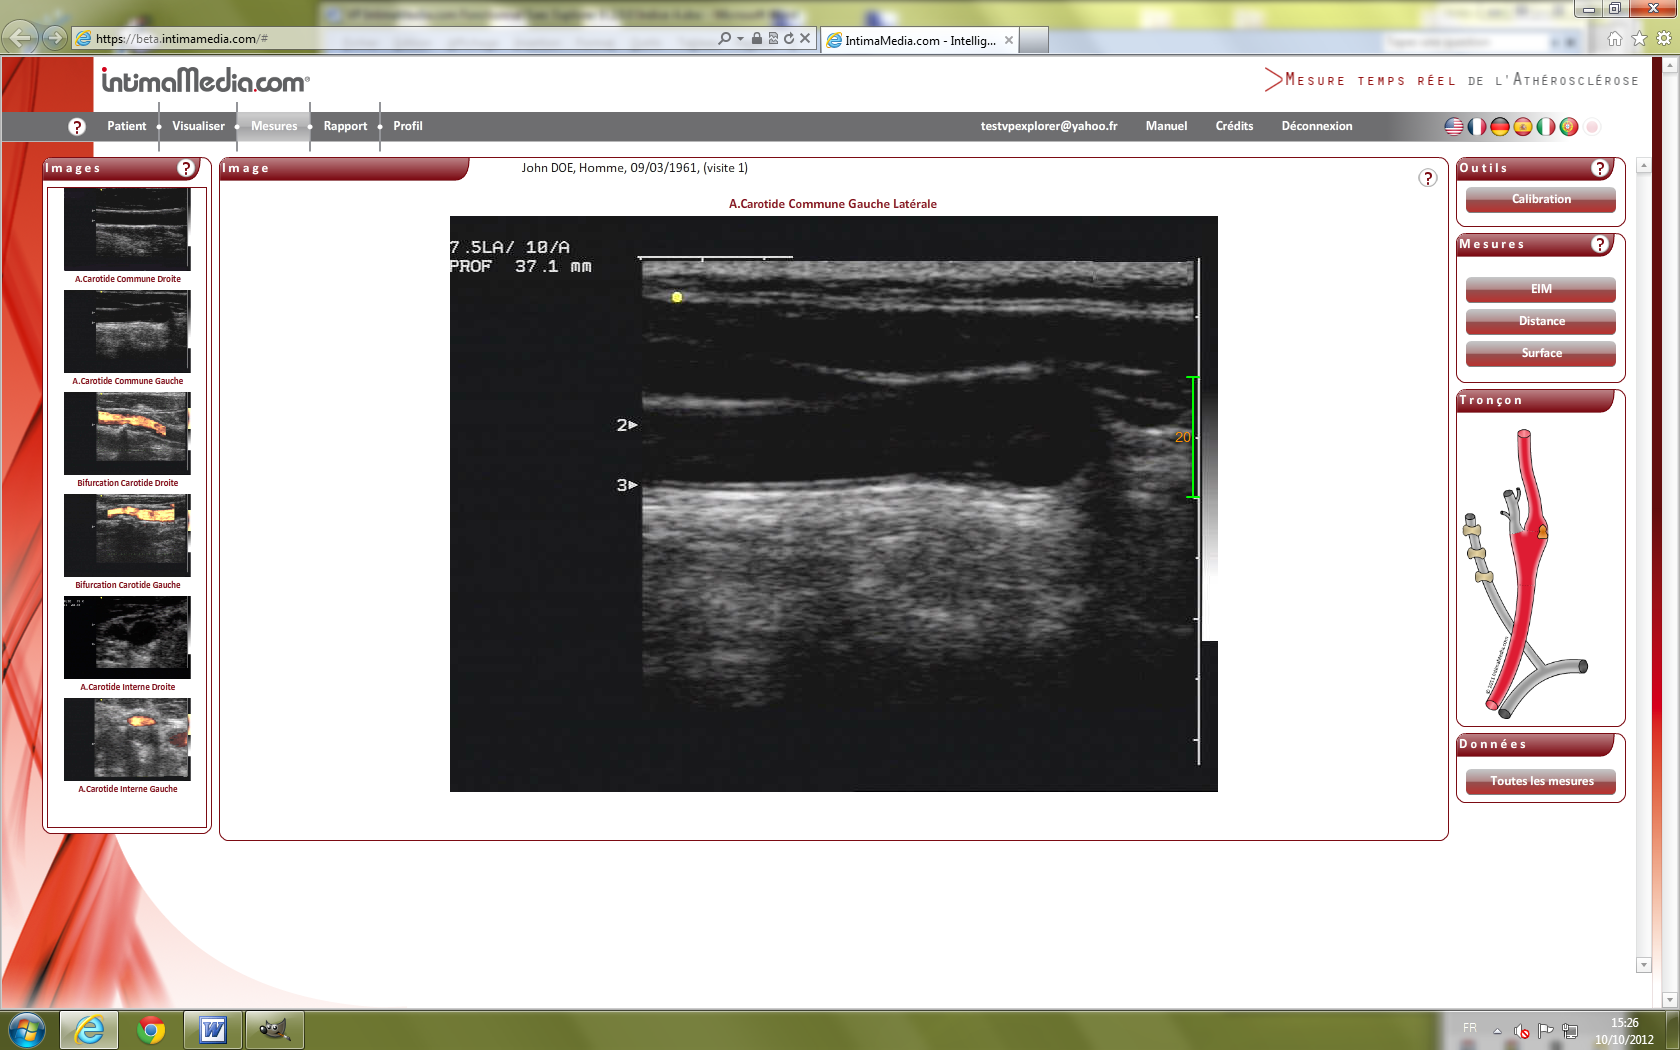

Images VP IExplorer 9. IntimaMedia 2.0.0 Fonctionnal

Test48.png